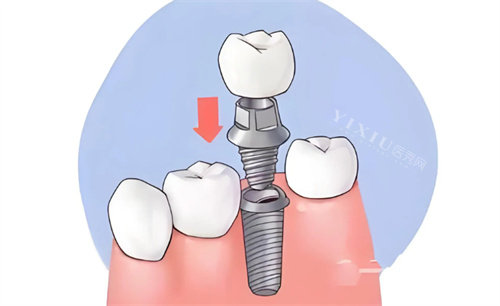

基台与牙冠费用

基台作为连接种植体与牙冠的关键部件,需具备更准一些的匹配度与稳定性。伊诺配套基台多采用与种植体同质的纯钛材质,价格在每颗 800 - 1200 元,全口 4 颗基台费用约 3200 - 4800 元。牙冠方面,若选择性价比高的国产全瓷牙冠,每颗价格在 1000 - 1500 元,一整排 14 - 16 颗牙冠,费用约 14000 - 24000 元;若选用进口高端全瓷牙冠,如德国威兰德、美国 3M 拉瓦等,每颗价格超 3000 元,牙冠总费用将大幅增加。